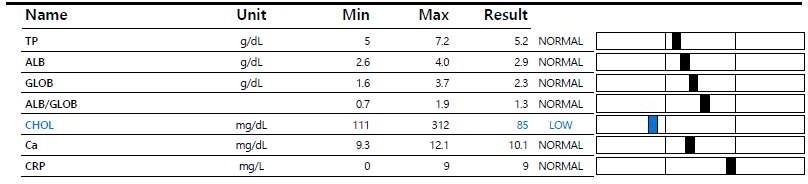

[혈액 검사]